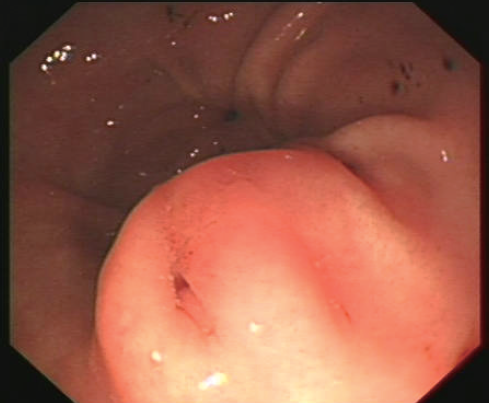

异位胰腺多位于胃窦,典型的异位胰腺中央有特征性的脐样凹陷(图7),超声内镜下显示位于黏膜下层的中高回声病变,内部呈现管状结构,而少数位于固有肌层或浆膜下的,显示为内部回声不均匀、形状不规则、边界不清晰。

图7 胃镜:典型异位胰腺中央特征性的脐样凹陷